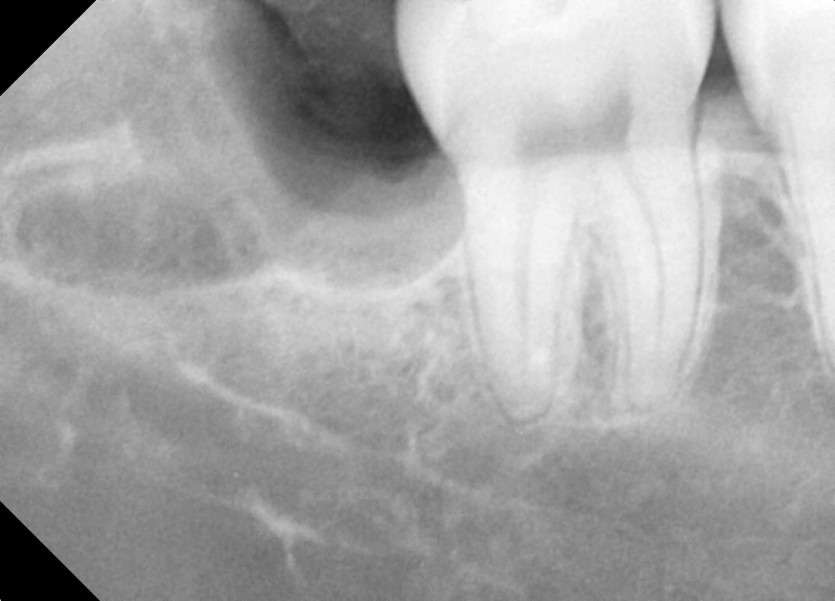

#38,48 사랑니 발치

구강 외과 전문의가 당일 발치했습니다.